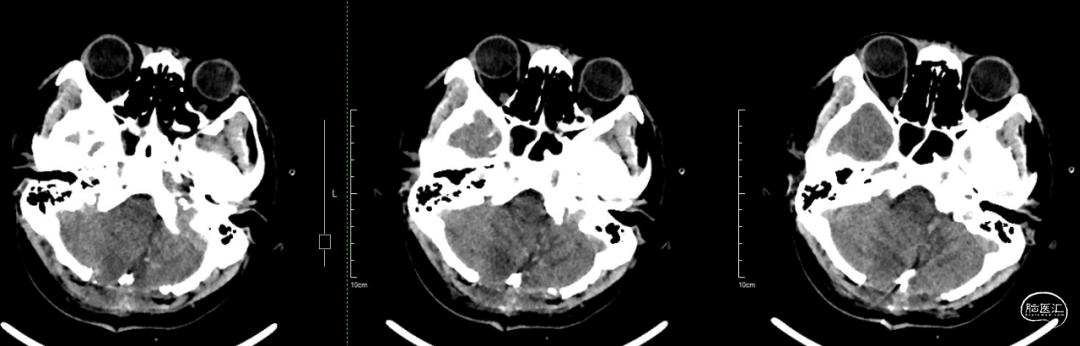

术后当天CT:肿瘤全切,术区无出血,幕上脑室积血,考虑术中出血倒灌所致。

术后一周CT:脑室积血基本吸收。